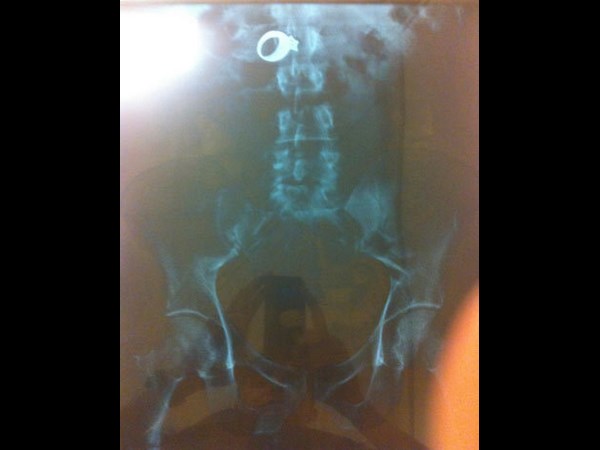

மருத்துவ உலகம் கண்டு வியந்த எக்ஸ் ரே படங்கள் இவைதான்

இதில் இவரது தலையில் ஊசி உள்ளது.